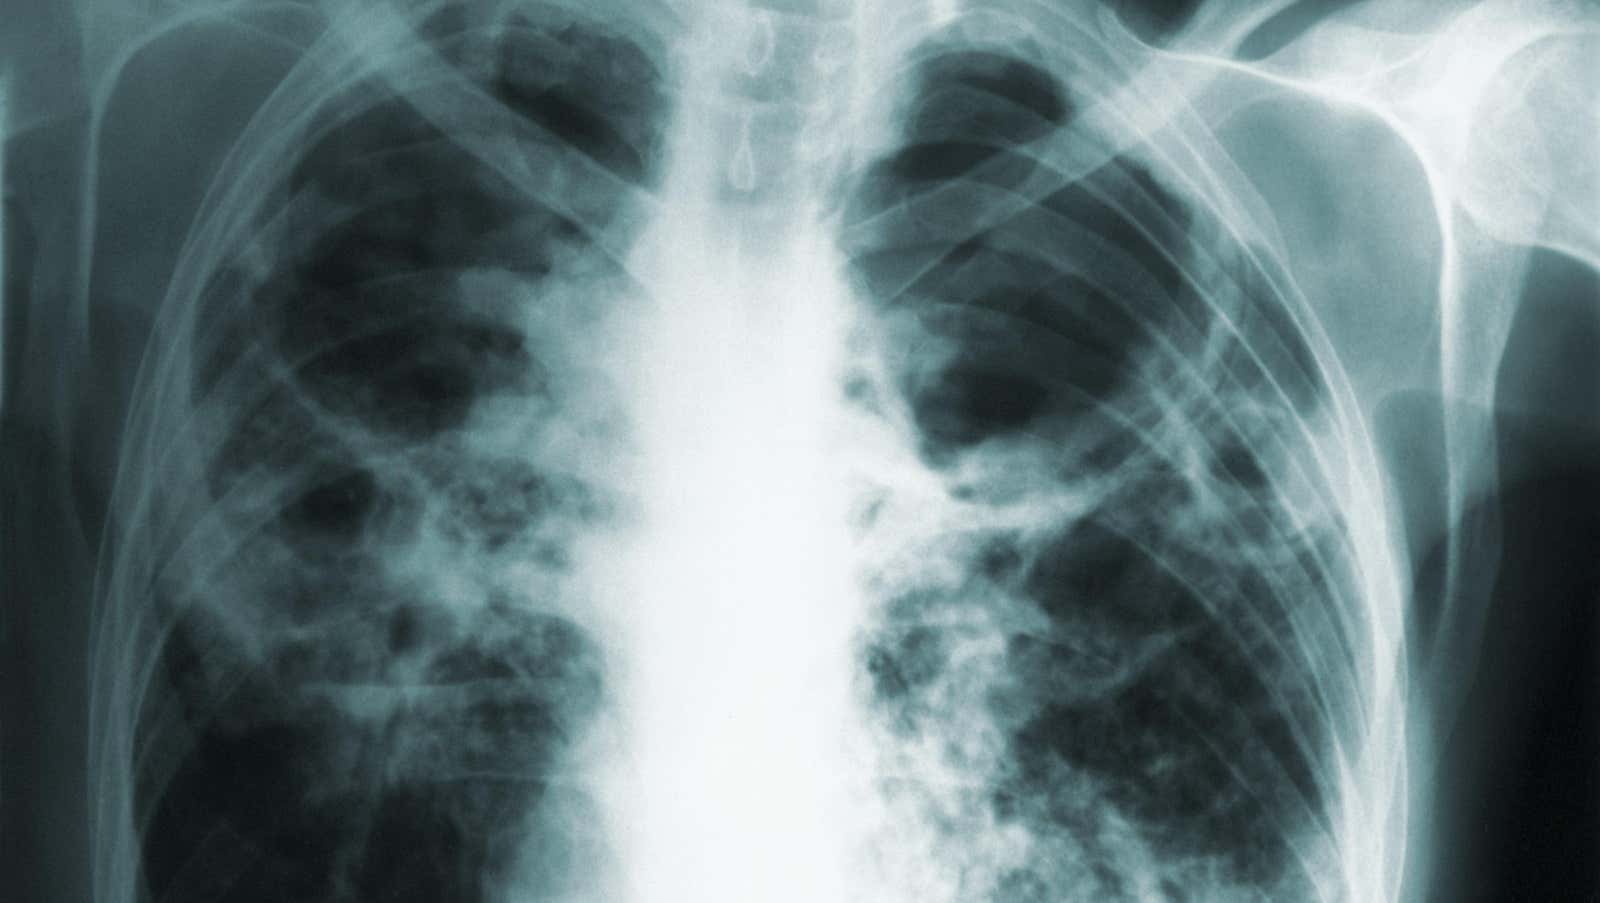

La tuberculosis, o TB, es causada por Mycobacterium tuberculosis. Muchas personas infectadas con la bacteria de la tuberculosis no se enferman y, a menudo, la infección entrará en un estado latente, donde los niveles de la bacteria permanecen bajos y las personas no se enferman ni son contagiosas para los demás. Sin embargo, si no se trata, la infección puede reaparecer e incluso convertirse en una amenaza para la vida, especialmente en personas con sistemas inmunitarios debilitados. La tuberculosis activa generalmente afecta los pulmones y causa síntomas respiratorios, pero la infección también puede migrar a otras partes del cuerpo.

Según The News Tribune, la mujer incumplió la orden judicial inicial y las posteriores obtenidas por el departamento de salud. Pero la gota que colmó el vaso parece haber ocurrido este enero. En una petición presentada el 11 de enero, el departamento afirmó que la mujer había tenido recientemente un accidente automovilístico. Un día después, buscó atención en una sala de emergencias por dolor en el pecho y le hicieron radiografías. Según los informes, la mujer no informó a la sala de emergencias de su estado de tuberculosis, lo que podría exponerla a ella y a otros a la infección. Su confidencialidad incluso llevó al personal a suponer que sus síntomas podrían haber sido causados por cáncer de pulmón. Y, según los informes, la mujer también dio positivo por covid-19 al mismo tiempo.